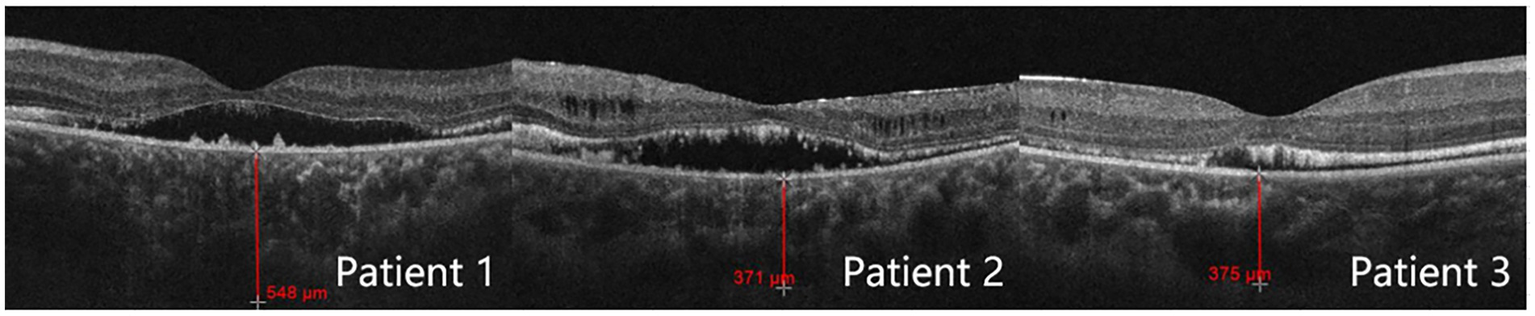

Optical coherence tomography

For all three patients, the OCT optic disc examinations revealed an increase in the cup/disc ratio and a decrease in the mean retinal nerve fiber layer (RNFL) thickness. The OCT macula examinations revealed that the central foveal thickness (CFT) increased, and the subfoveal choroidal thickness (SFCT) increased (Table 3). There was serous detachment of the foveal neuroretina, and the choroid thickened (Figure 3).

| Patient | Mean RNFL thickness (ÎĽm) | CFT (ÎĽm) | SFCT (ÎĽm) | C/D |

|---|---|---|---|---|

| 1 | 61 | 258 | 548 | 0.85 |

| 2 | 58 | 208 | 371 | 0.71 |

| 3 | 90 | 220 | 375 | 0.78 |

Test results of optical coherence tomography.

RNFL, retinal nerve fiber layer; CFT, central foveal thickness; SFCT, subfoveal choroidal thickness; C/D, cup/disc ratio.

Figure 3

Subfoveal choroidal thickness measured by optical coherence tomography.

Moreover, some studies have suggested that even combining lens removal with trabeculectomy may not suffice in preventing postoperative refractory shallow anterior chamber (24). Of the three patients described in this study, the lens thickness was within the normal range in all three cases. Patient 2 underwent lens removal along with trabeculectomy, but still developed malignant glaucoma after the initial surgery. We thus speculate that, for ACG/ARB patients, the angle closure mechanism may not be due to pupillary blockage upon lens enlargement. Instead, the culprit may be the pressure from the posterior segment, which pushes forward the iris diaphragm and thus reduces the ACD (8). Quigley et al. (25) pointed out that the thickening choroid pushes the molded vitreous body forward, creating a high-pressure environment and causing vitreous conduction. The choroidal thickness of patients 1, 2, and 3 was 548, 371, and 375 μm, respectively. The study by Huo et al. (26) revealed that the mean subfoveal choroidal thickness in healthy adults was 288.43 ± 74.60 μm for the 31–40 years group and 278.05 ± 72.87 μm for the 41–50 years group. Notably, the choroidal thickness in our three patients was significantly greater than that of age-matched healthy adults in the corresponding age groups. Since ARB patients are usually young, the vitreous has a high degree of integrity and a low degree of liquefaction, and choroidal thickening passes greater pressure onto the anterior chamber. Once the anterior vitreous contacts the ciliary body and the lens, the effective diffusion area decreases, and the reflux of the aqueous humor occurs. Surgeries such as trabeculectomy create additional outflow channels and can further increase the pressure gradient between the anterior and posterior segments. The lens-iris diaphragm moves further forward and causes angle closure. At this point, the aqueous humor does not have anywhere else to go other than entering the vitreous cavity. Therefore, for patients, especially younger patients with a thicker choroid, glaucoma drainage surgery should be selected with extra caution since the probability of postoperative malignant glaucoma is very high.